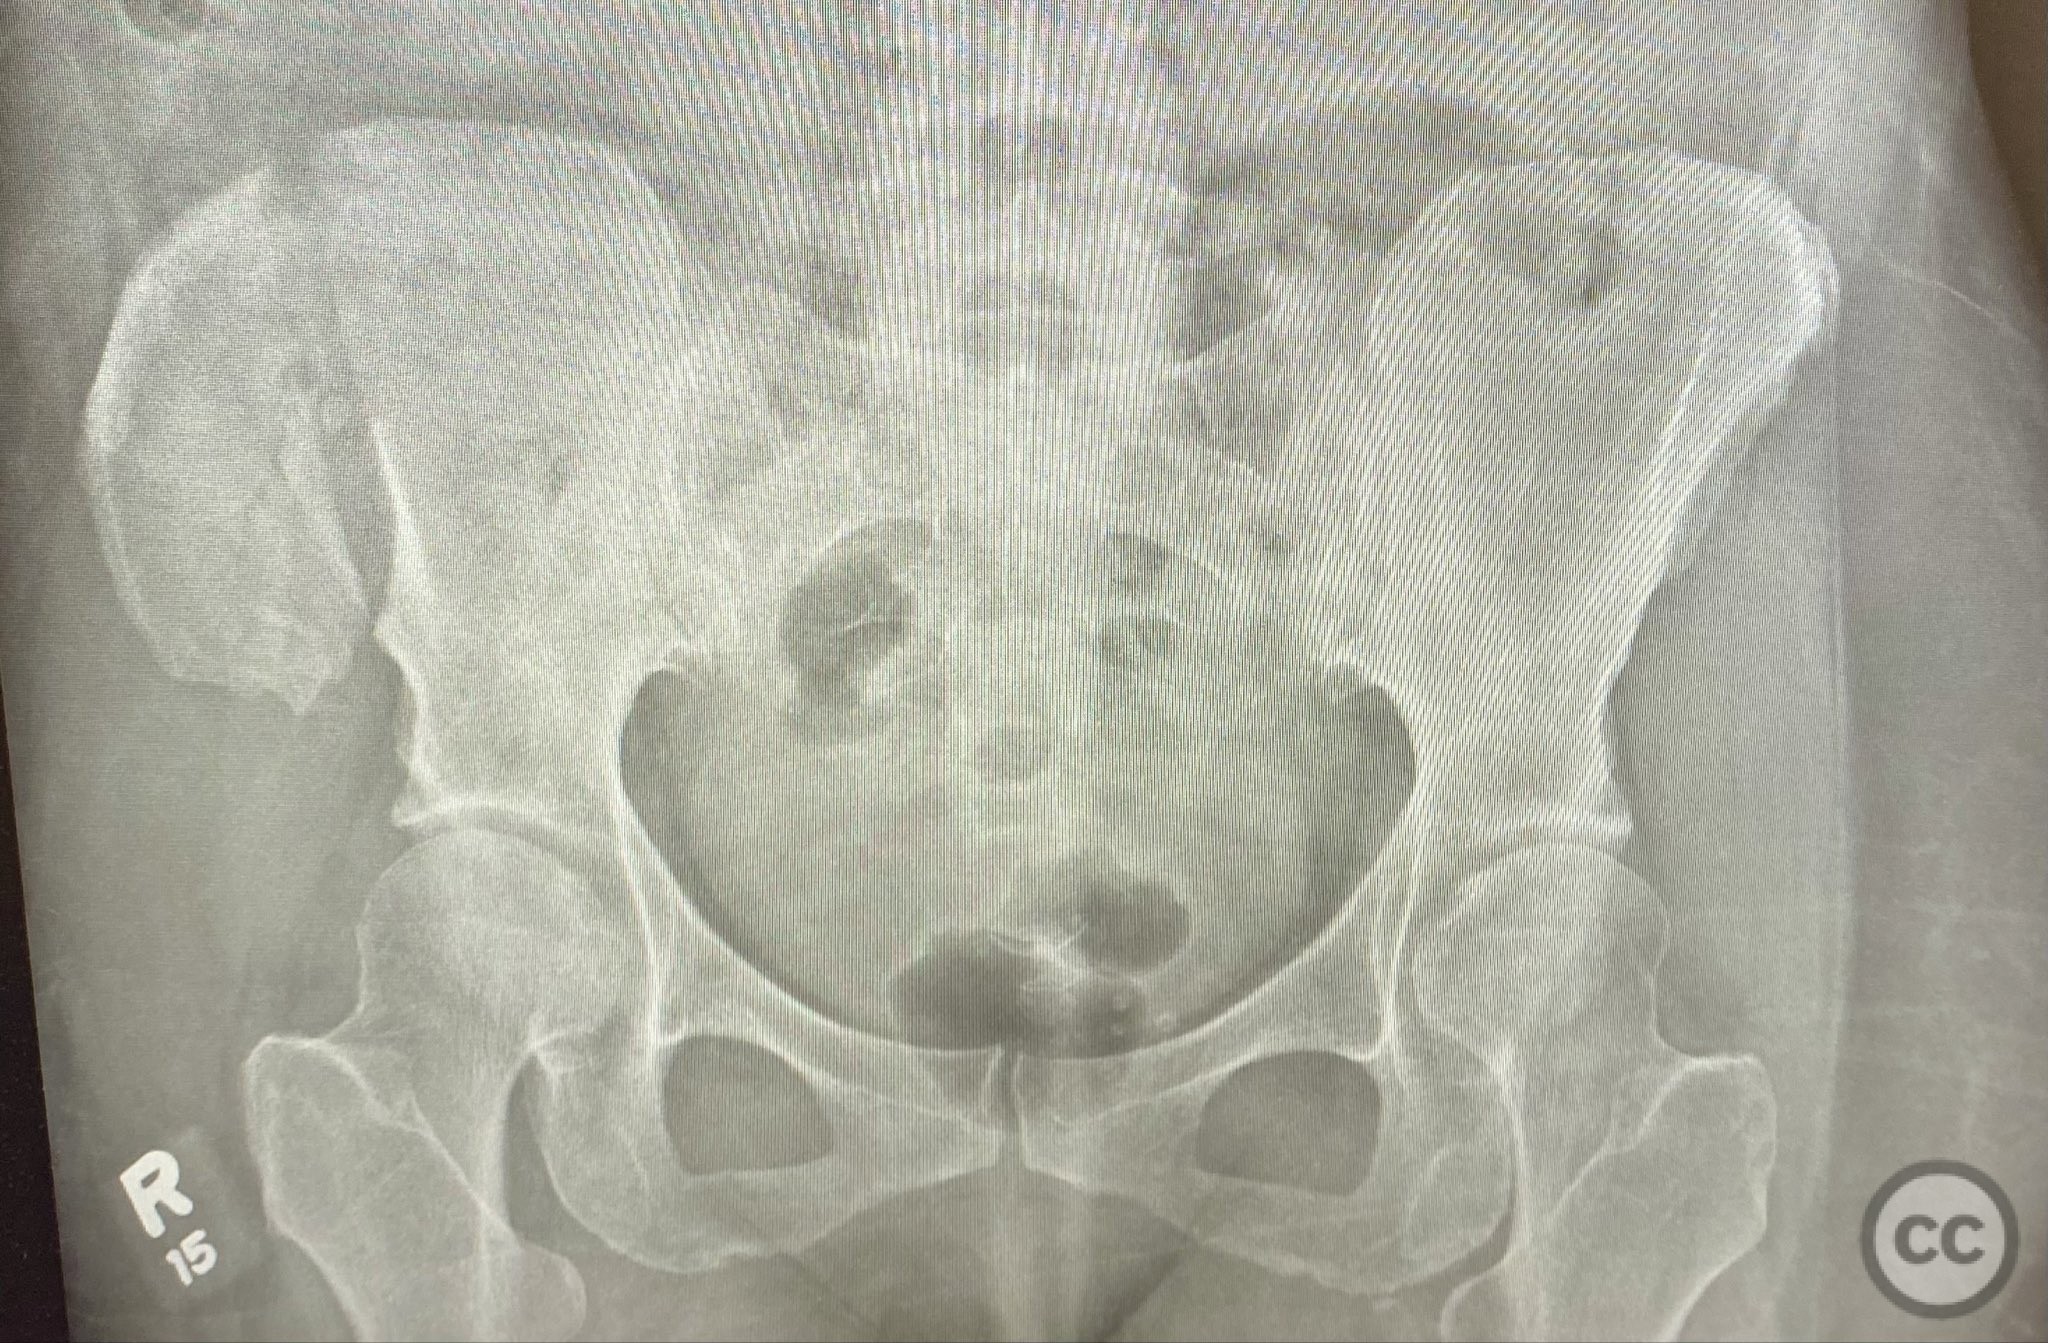

Clinical Details

Clinical and radiological findings:  A middle-aged patient sustained a closed, displaced, and comminuted fracture of the right os ilium following a fall from height. Initial AP pelvic radiograph and 3D surface rendered imaging demonstrated significant comminution, displacement, and poor bone quality. The patient was unable to mobilize due to pain. No associated neurovascular deficit or additional pelvic ring injury was reported. AO/OTA classification: 61B2.2 (partial articular, comminuted iliac wing fracture).